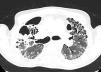

A 67-year-old male with a history of progressive pulmonary fibrosis after COVID-19 (Fig. 1), referred for evaluation for lung transplant at last pneumology follow-up, was admitted to the hospital because of severe respiratory insufficiency. His medical record included chronic lymphocytic leukaemia (in remission), pulmonary embolism and atrial fibrillation on anticoagulation. He presented with a recent onset of dyspnoea, cough with purulent sputum, fever and increased oxygen requirement. Blood pressure was 122/65mmHg, pulse 100bpm, SaO2/FiO2 112, and a respiratory rate of 40bpm with scattered bilateral crackles. Blood gases showed respiratory acidosis (pH 7.27, pCO2 116mmHg, pO2 38mmHg, HCO3 53.3mM/L). A chest X-ray revealed a known interstitial pulmonary infiltrate without significant changes compared to his previous one. Laboratory studies showed an increased C-reactive protein (136.0mg/L), leukocytosis (14.70×10^3/μl), and neutrophilia (10.90×10^3/μl). Since the patient had a do-not-intubate order, he was admitted to the IRCU.